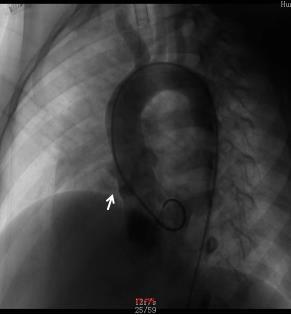

室間隔缺損是兒童最常見的先天性心臟病,近年來,隨著兒童先心病介入技術(shù)的不斷提高,絕大多數(shù)膜周部及肌部室缺都可以通過介入治療得到痊愈,一些位置異常的先心病也開始有了介入的機(jī)會。8歲的“萌萌”(化名)就是一位“嵴內(nèi)型”小室缺的患兒。來我院前家屬已經(jīng)咨詢了多家醫(yī)院,如果選擇開胸手術(shù),由于缺損小,不易尋找缺口,手術(shù)難度增加,并且創(chuàng)傷大,身體留下手術(shù)疤痕,心理也將受到影響,如果長期隨訪影響身心健康、學(xué)習(xí)和生活。為此“萌萌”家人來到了我的兒童心血管門診面診??紤]到“萌萌”為嵴內(nèi)型小室缺,并多次跟心臟超聲團(tuán)隊(duì)商討后,我們團(tuán)隊(duì)決定給“萌萌”進(jìn)行嵴內(nèi)型室缺封堵治療。術(shù)中造影發(fā)現(xiàn),“萌萌”的室缺分流口2.1mm,距離主動脈瓣很近,應(yīng)用常規(guī)室缺封堵器可能會造成明顯的主動脈瓣反流。根據(jù)造影結(jié)果,醫(yī)生跟家屬再次溝通后,決定應(yīng)用二代動脈導(dǎo)管未閉封堵器(ADO-Ⅱ)進(jìn)行封堵,此封堵器質(zhì)地更加柔軟,延展性強(qiáng),在封堵室缺的同時可最大限度的降低對主動脈瓣的損傷,術(shù)后心律失常的風(fēng)險也會減少。短短1個多小時,“萌萌”的室缺成功封堵,主動脈瓣沒有任何影響,“萌萌”的室缺治愈,術(shù)后4天出院,幾乎無手術(shù)疤痕。隨著介入治療技術(shù)的提高和介入器材的豐富,一些特殊類型的先心病也可以通過介入治療獲得痊愈:包括嵴內(nèi)型室缺、細(xì)小導(dǎo)管型及嬰幼兒動脈導(dǎo)管未閉、冠狀動脈瘺、肺隔離癥等。介入手術(shù)具有眾多優(yōu)點(diǎn):手術(shù)時間短、恢復(fù)快、創(chuàng)傷低等,現(xiàn)在可降解封堵器也將面世,未來將成為兒童先天性心臟病或者某些肺血管疾病的治療首選,更好的呵護(hù)兒童健康成長。劉麗萍副主任醫(yī)師門診:湖南省人民醫(yī)院(天心閣院區(qū)),小兒心血管門診,每周五上午。綠色熱線:0731-83929461;